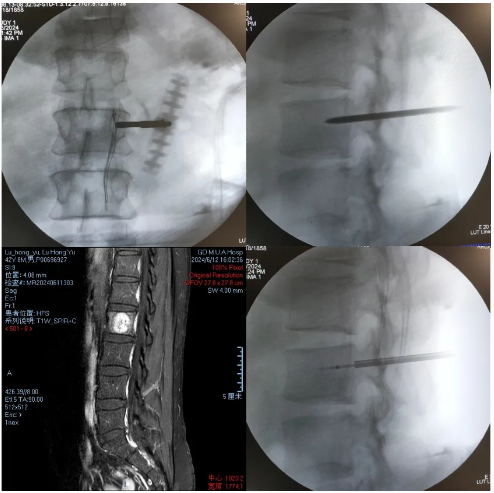

·患者陆某某,男,42岁,因反复腰背部疼痛1年余入院。腰背痛VAS评分6分。

·诊断:腰2椎体痛性血管瘤

首例局麻下智能控温射频消融治疗椎体痛性血管瘤

患者手术全程保持清醒,射频消融过程中无任何不适。术后第一天佩戴腰围起床活动。术后腰背痛VAS评分3分。